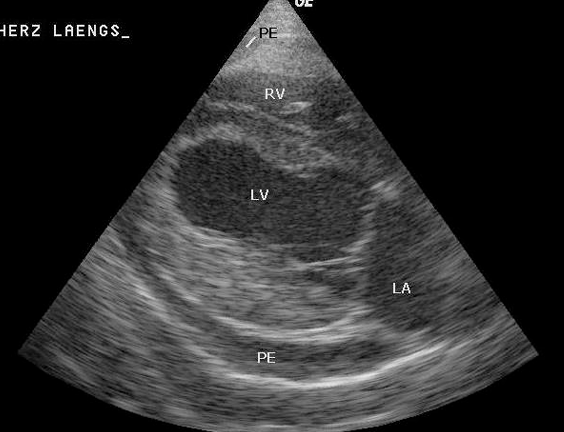

![]() | ์ฌ์ฅ๊ณผ ์ฌ๋ญ ์ฌ์ด์ Echo-free space (๋ฑ ๋ด๋ ์ชผ๊ทธ๋ผ๋ค์ด ๋ณด์) |

![]() | echo๊ฐ denseํ pericardium |